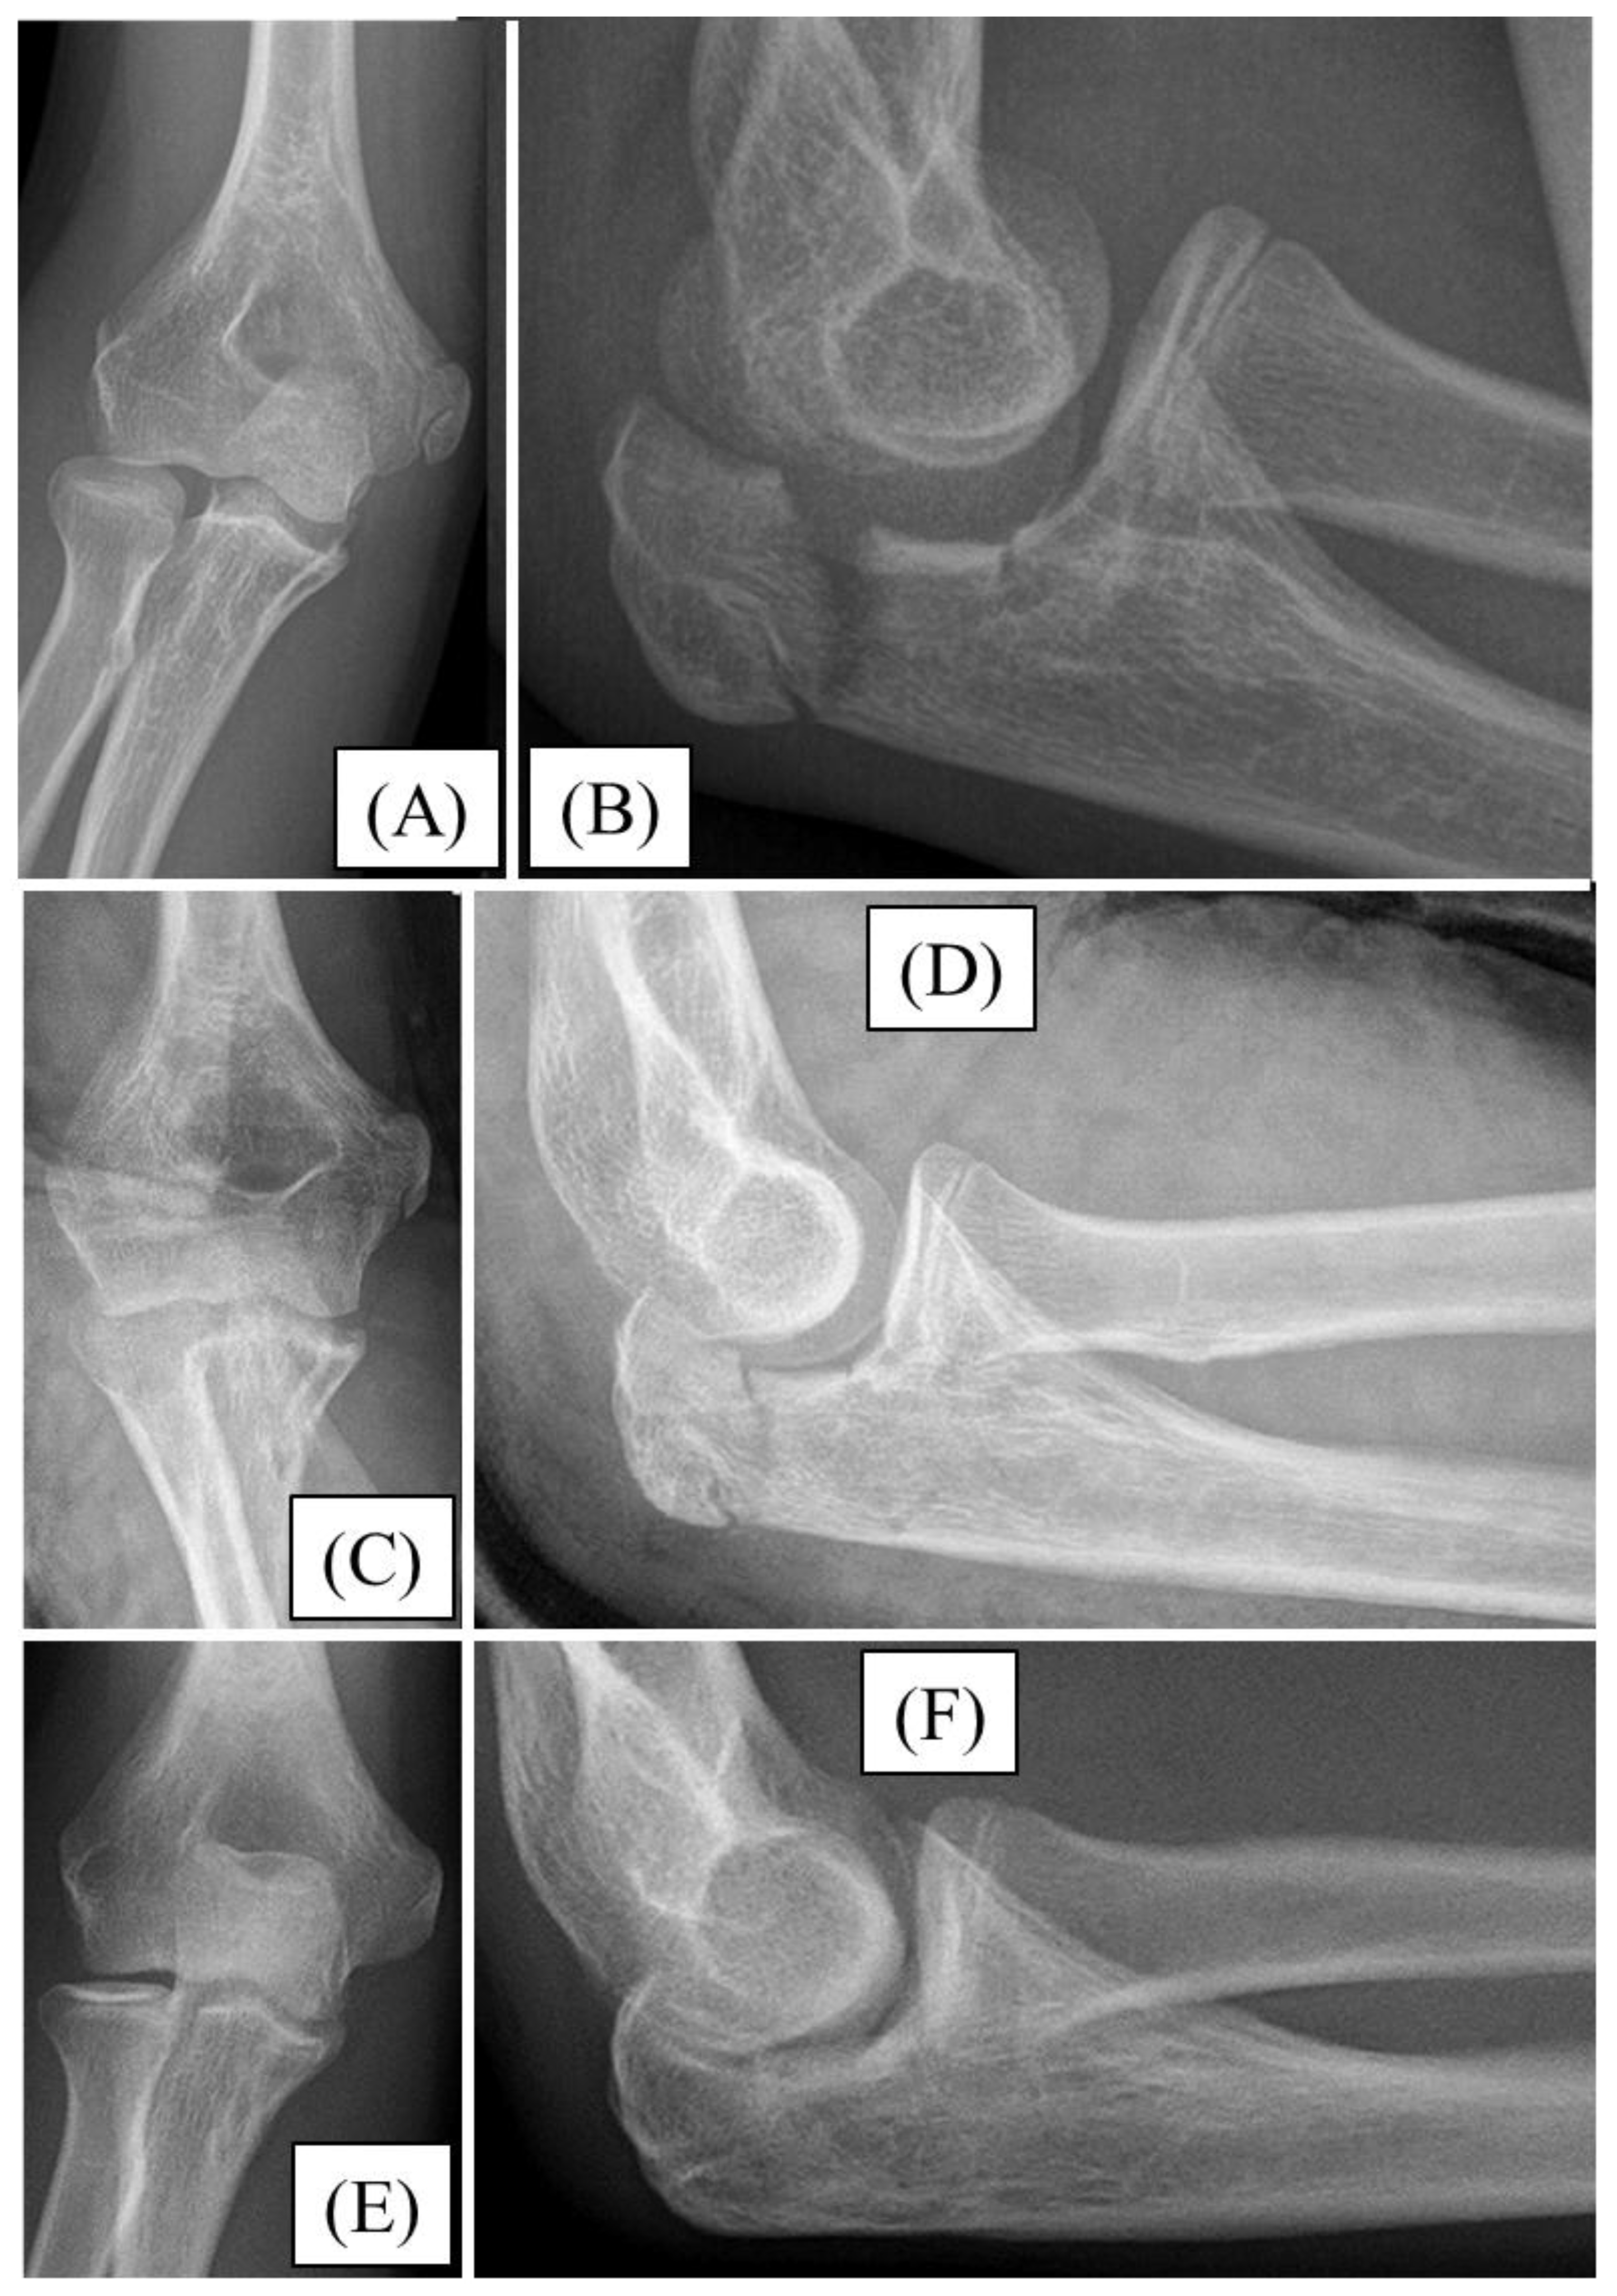

While cycling, a 12-year-old boy injured his left elbow. Initial X-rays confirmed a Mayo type II/A olecranon fracture (Figure 1A). Due to the formation of joint steps, surgical intervention was necessary. Throughout the open approach, the fracture was reduced to an anatomical position and temporarily fixed with two K-wires (Figure 1B). After the removal of the K-wires, the absorbable PLGA pins were placed into the cavity previously created by the wires. Subsequently, compression was achieved by PDS loops placed in a drilled canal distal to the fracture to ensure proper stability (Figure 1D). A right-angle dorsal cast was employed to immobilize the left upper limb for three weeks, followed by active physiotherapy treatment.

During follow-up, the child’s range of motion (ROM) in the elbow gradually improved with regular physiotherapy. Three months after the surgery, the elbow ROM was fully restored. At the one-year follow-up, the motion of the left elbow was identical to that of the unaffected side. No sensitivity or irritation was reported around the surgical site. Follow-up X-rays showed complete healing of the fracture site with full joint congruence (Figure 2). One year after the operation, the child was symptom-free and has returned to everyday sports activities.

Figure 1. Primary X-ray of an olecranon fracture sustained by a 12-year-old boy, from lateral view (A). Fluoroscopic images after open reduction and temporary K-wire fixation (B-C). Intraoperative photograph showing the two parallel resorbable pins and a PDS compression loop (D). Postoperative X-rays demonstrate good alignment and perfect articular congruency from lateral (E) and AP (F) aspects.